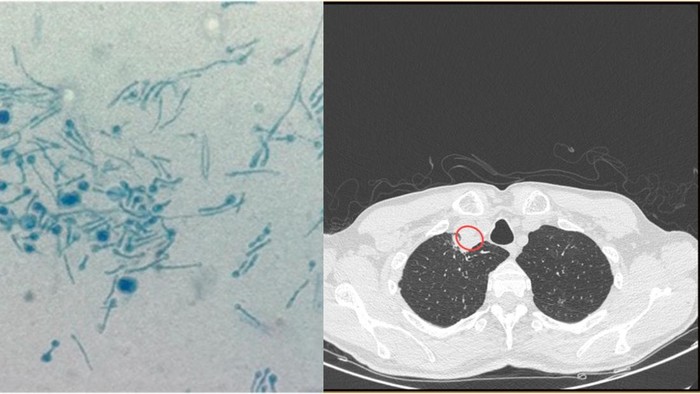

Dokter melakukan rontgen dan CT scan pada pria itu. Hasil rontgen di dadanya terlihat normal, tetapi hasil CT scan menunjukkan abses paratrakeal di lehernya.

Dokter mendiagnosis pria itu dengan Chondrostereum purpureum, jamur tanaman yang menyebabkan penyakit daun perak pada tanaman. Daun perak menginfeksi kayu dan daun beberapa pohon, menyebabkannya berubah menjadi abu-abu keperakan.